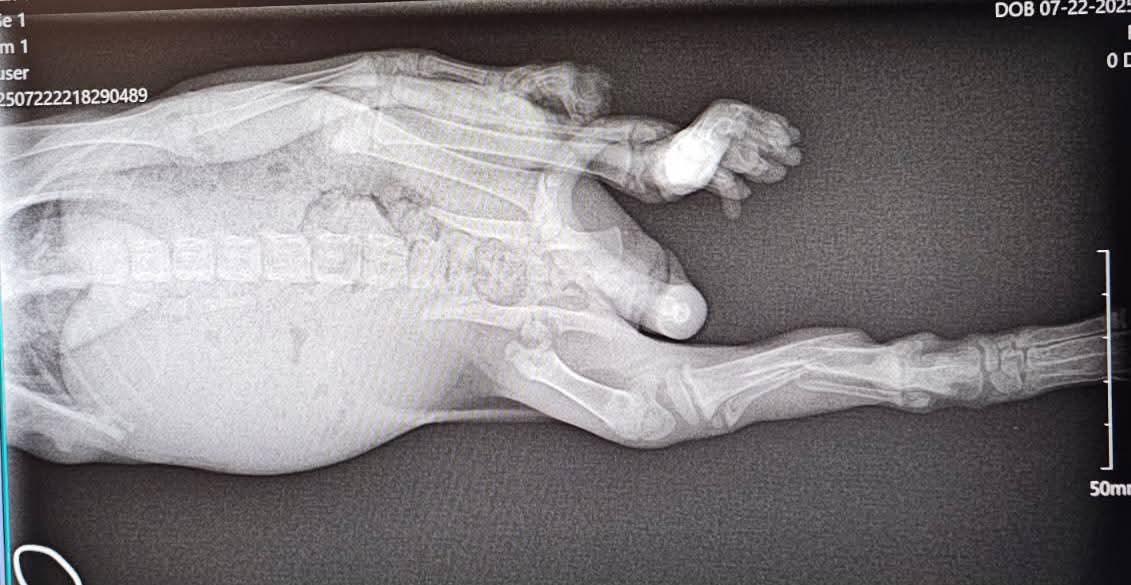

Meet Tomahawk, a sweet kitten who came to us with a compound fracture in one leg and a nasty fracture in another leg, which ended up with him needing an amputation. Despite such a rough start to life, this little guy is full of life and love, and just wants to be friends!! He's go-go-go! Who would like a snuggly, playful tripod kitten?

There is still the possibility that Tomahawk will need more surgery on his right hip, but we are hopeful that it will not be necessary. We will reevaluate when he is about 6 months old. If surgery is necessary, we will be covering the cost.